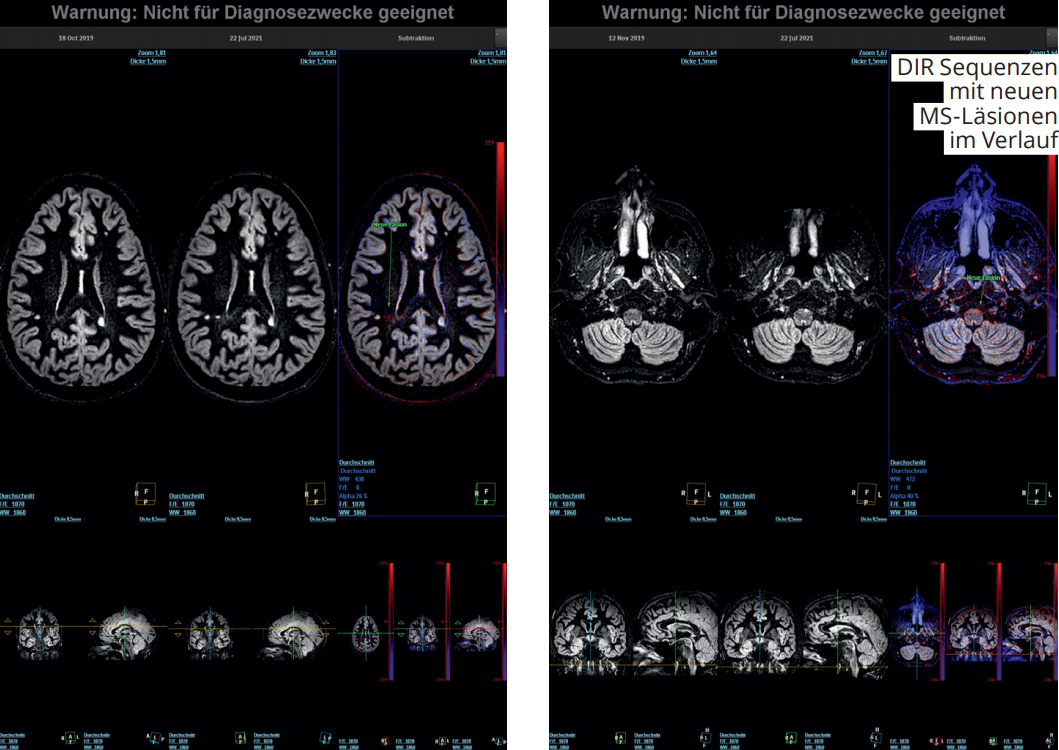

Multiple Sklerose (MS) Diagnostik: Schneller und genauer!

Zielgenaue MS-Verlaufskontrollen mithilfe der Subtraktions-Applikation der Fa. Philips.